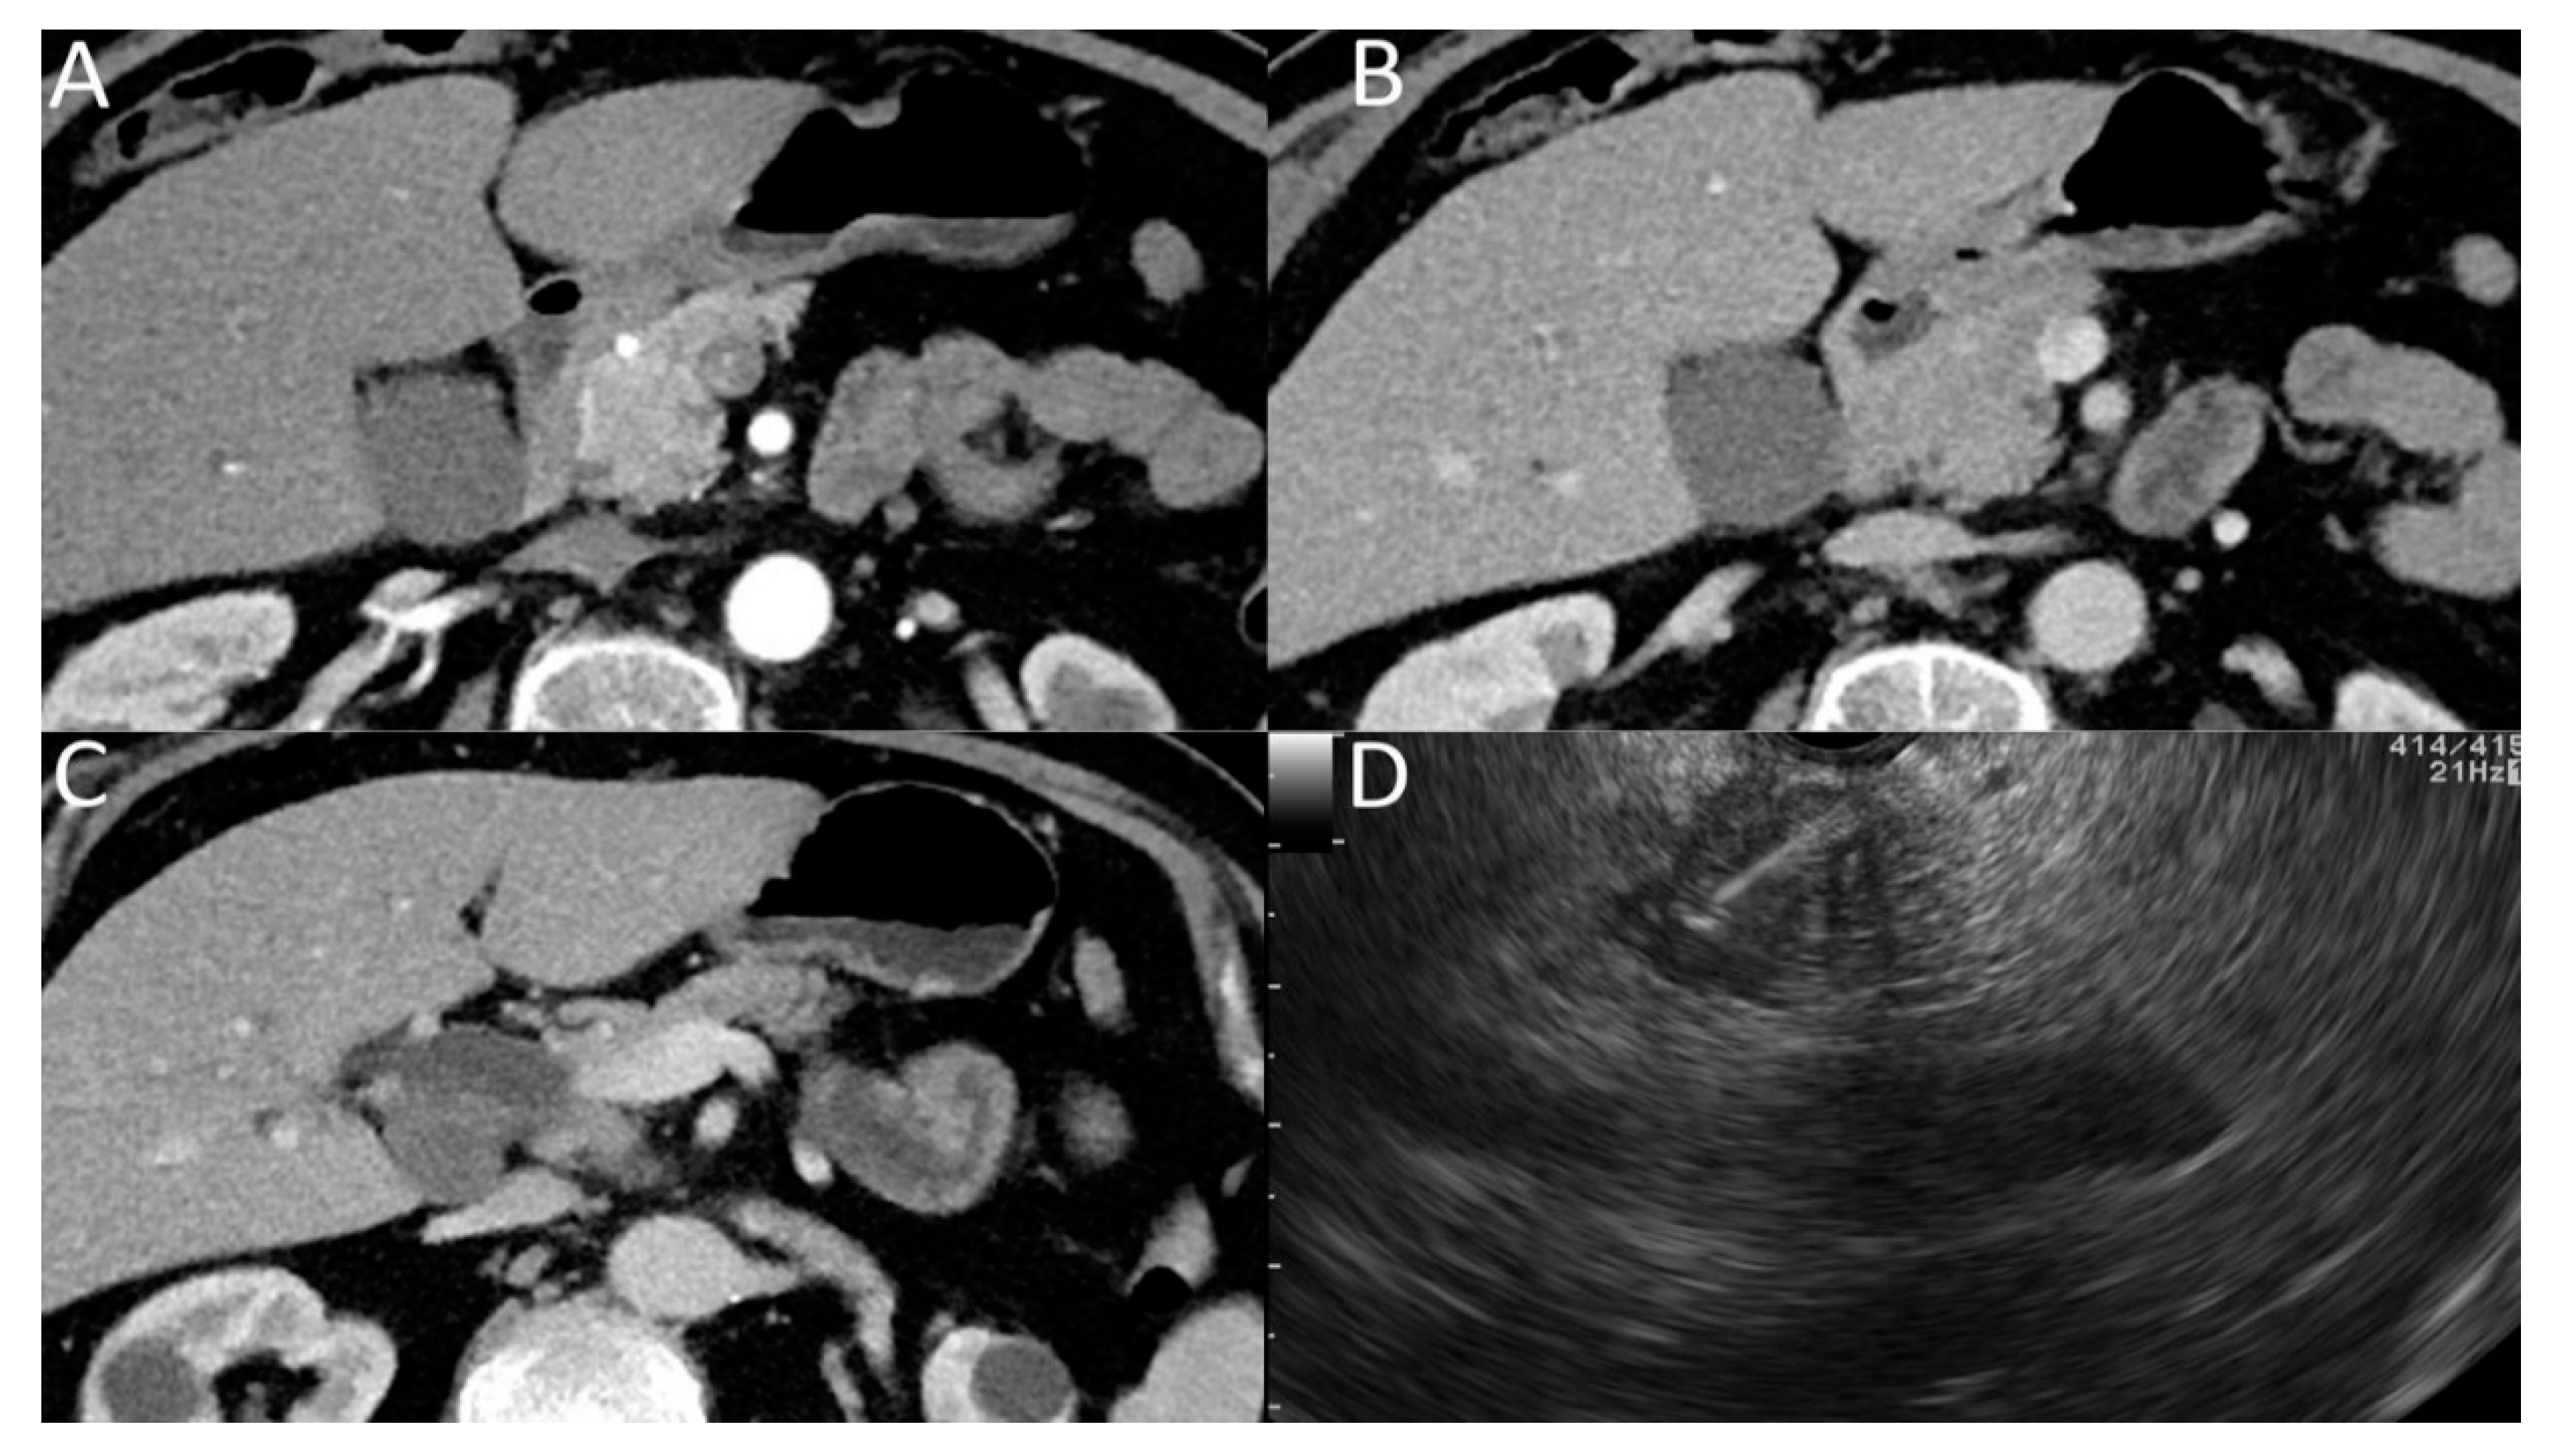

Improvement of the Diagnosis of Isoattenuating Pancreatic Carcinomas by Defining Their Characteristics on Contrast Enhanced Computed Tomography and Endosonography with Fine-Needle Aspiration (EUS-FNA)

3.2. Secondary Signs of Isoattenuating Pancreatic Carcinomas on CT

3.3. EUS Findings and the Role of EUS-FNA in the Confirmation of Pancreatic Cancer